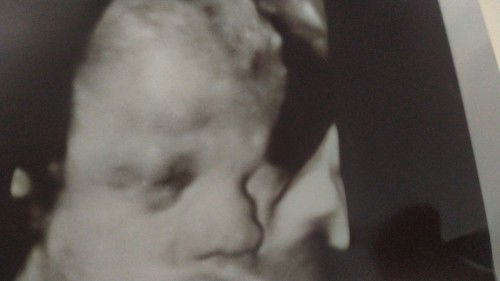

Kehamilan 32week

Alhamdulillah si Dede sehat, tpi di lihatin umi nya malu2 nih.. mukanya ditutupin dan pura pura tidur.. sehat sehat selalu di dalam nak😘